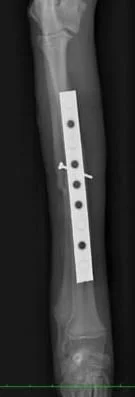

右前肢

橈骨・尺骨ともに癒合してますし、

橈骨の髄腔もきちんと確認できます。

極端な骨硬化像も認めないので経過観察終了としました。